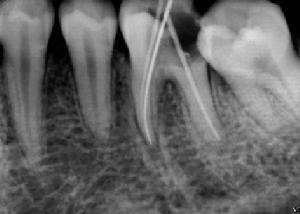

3.對牙髓狀況判斷失誤:比如小的穿髓孔未被發現而直接充填。